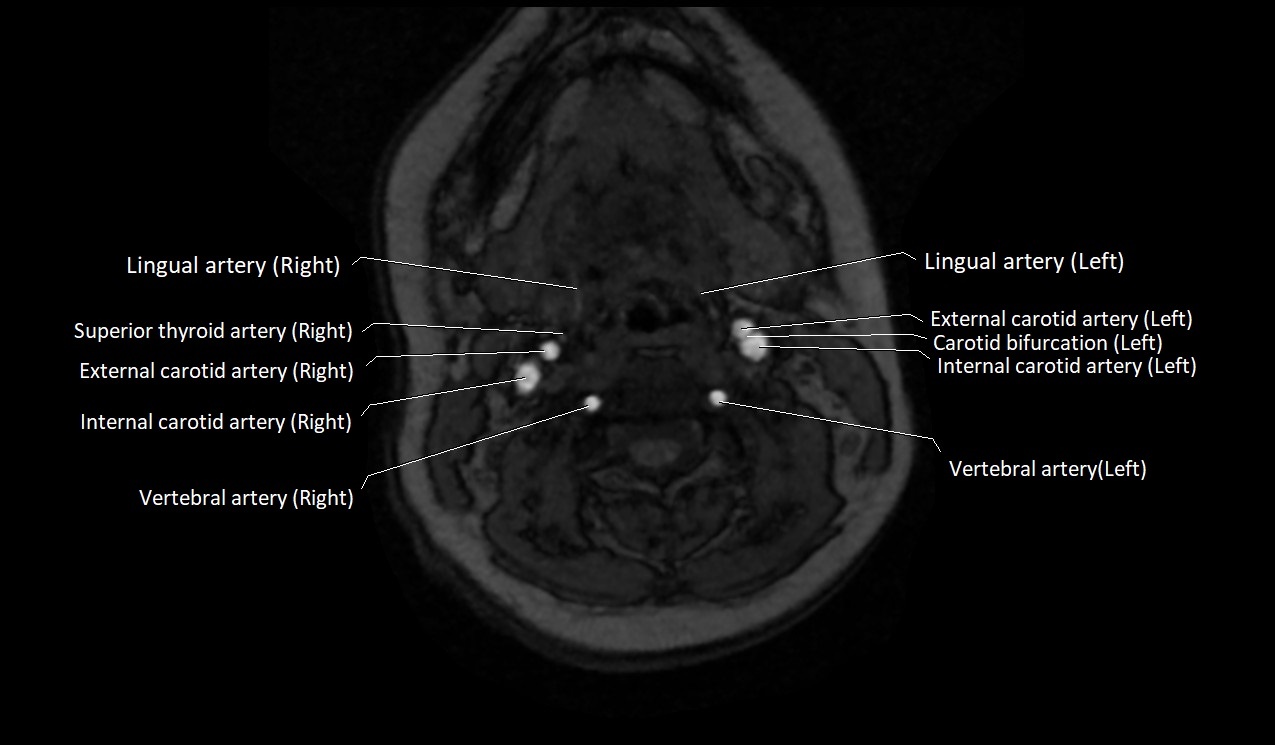

MRI Appearance:

• T1-Weighted Images:

• Appears as a tubular, hypointense (dark) structure relative to muscle

• May show flow void if the blood flow is fast

• T2-Weighted Images:

• Typically hypointense or isointense to muscle, but can be hyperintense if slow flow or stasis is present

MRI images

image